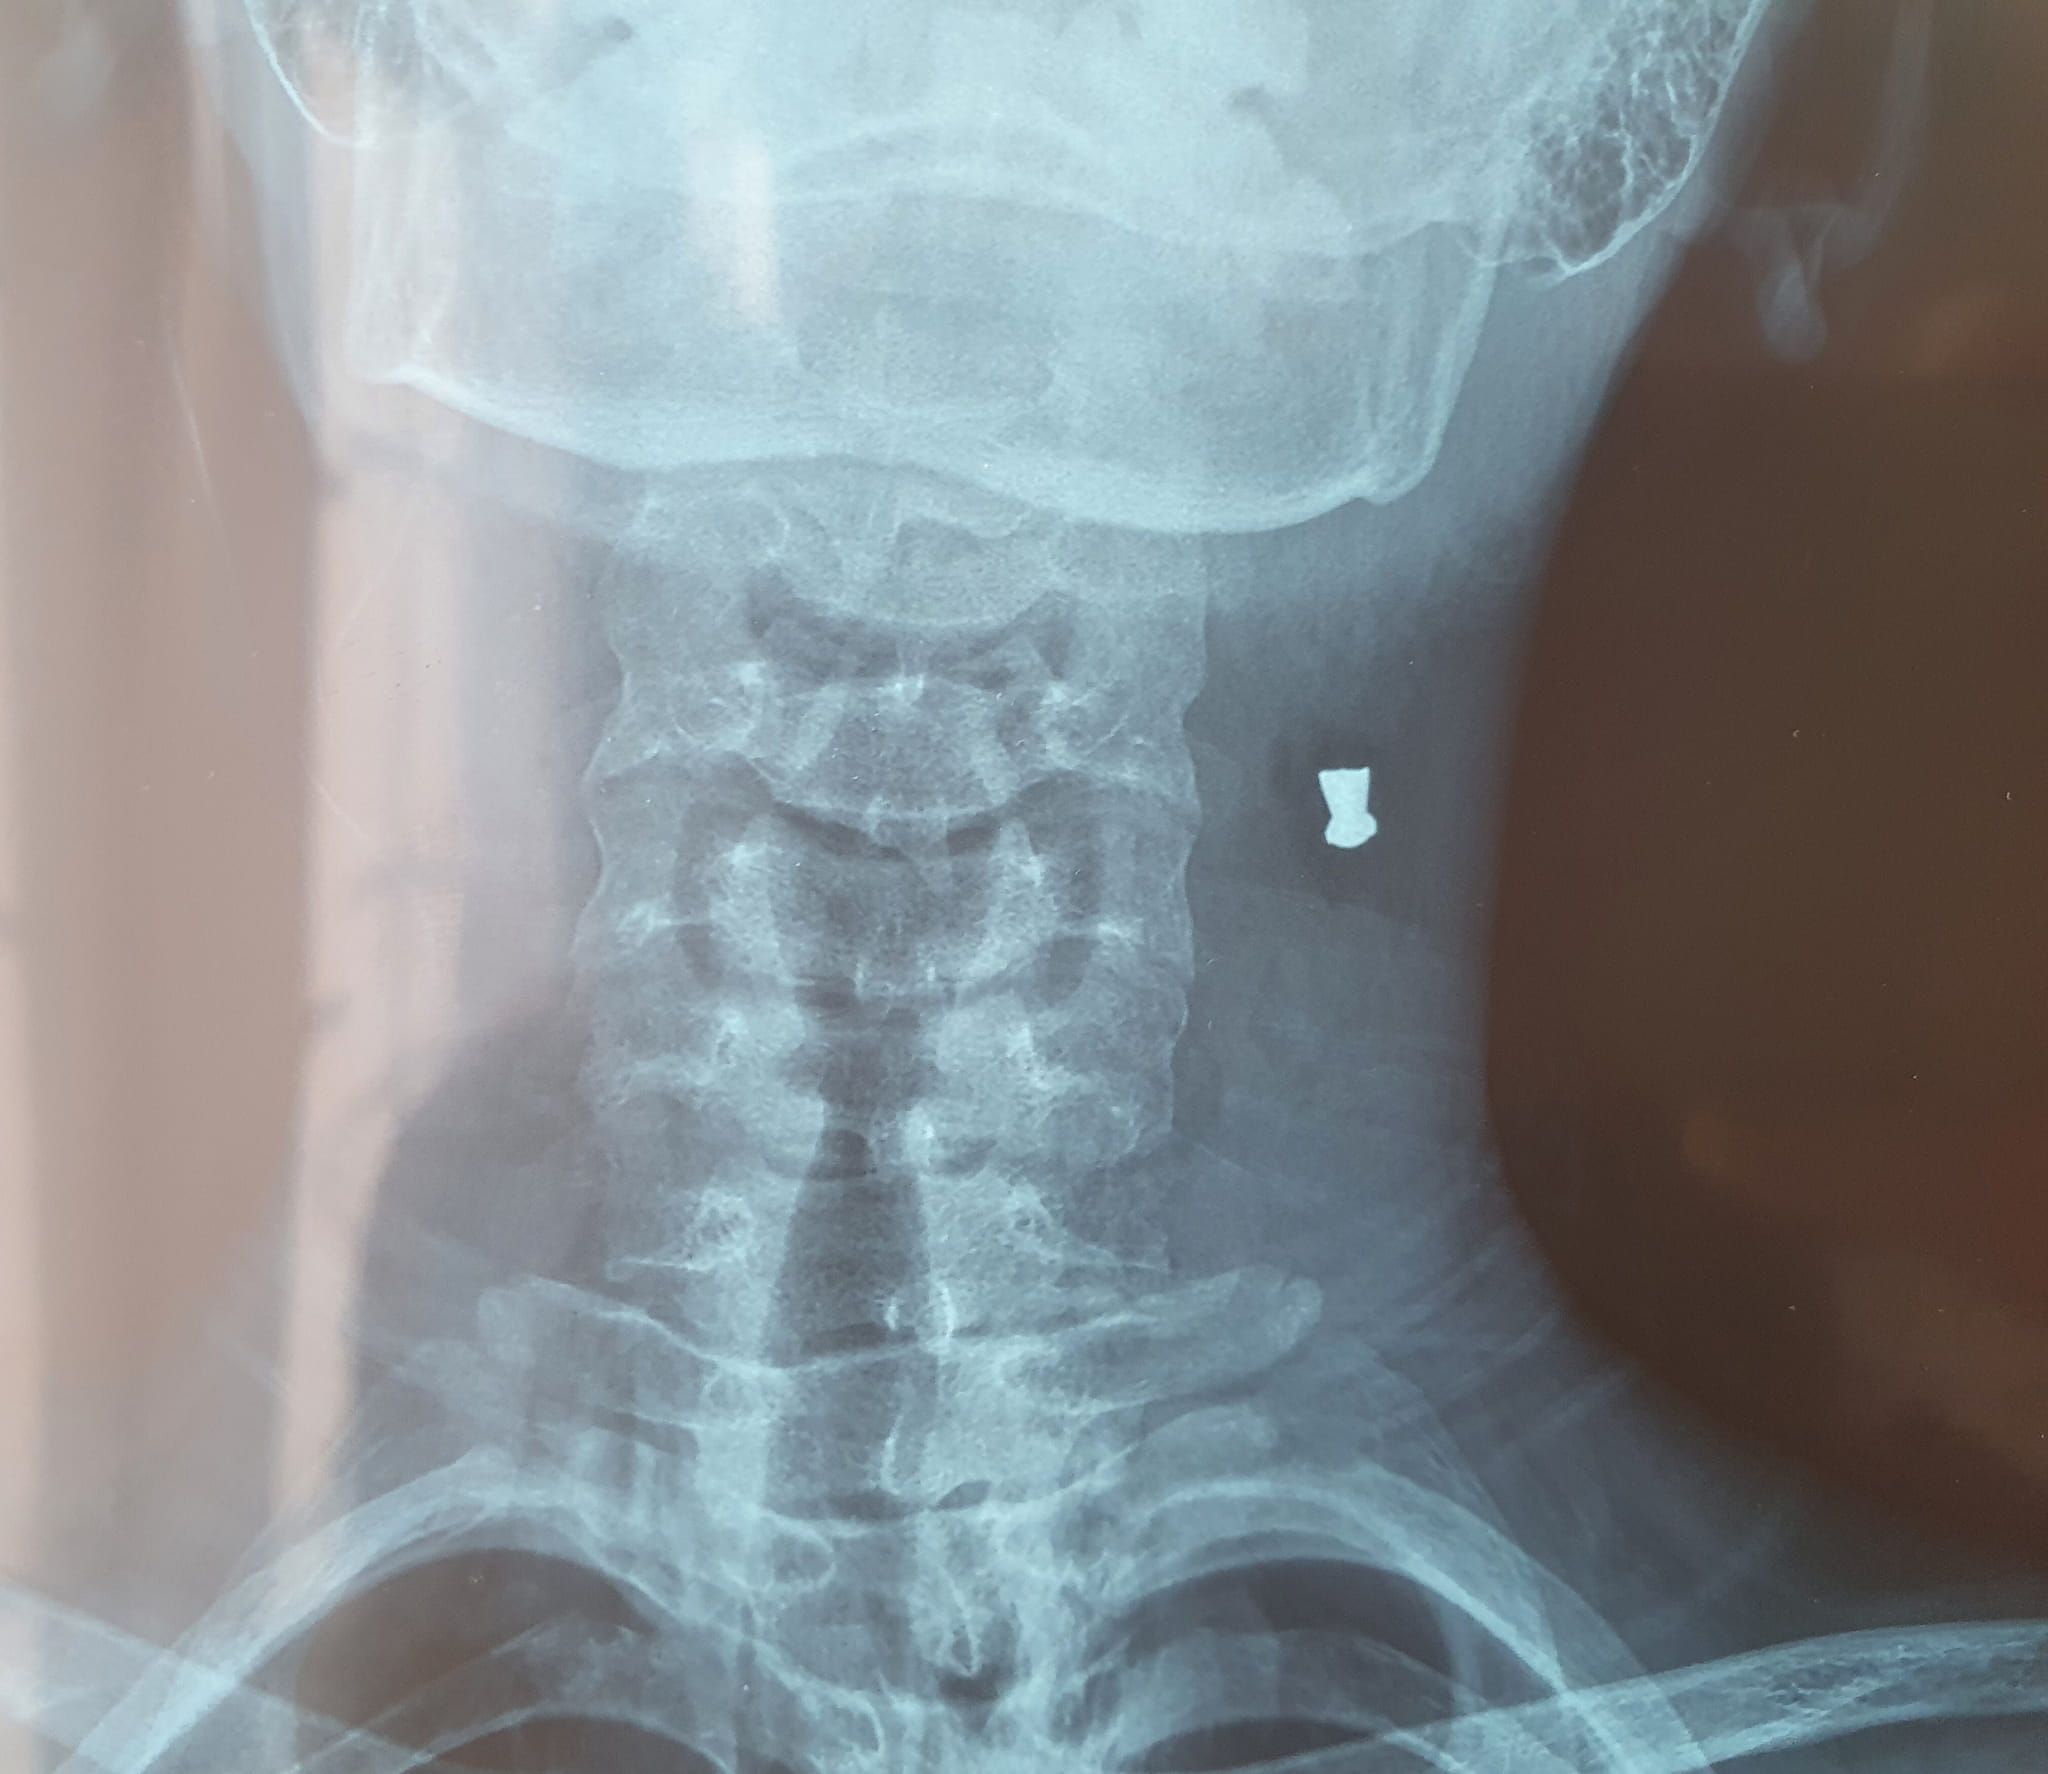

У Львівській області підліток вистрілив із гвинтівки товаришу в шию. Дитину госпіталізували до львівської обласної дитячої лікарні «Охматдит».

Про інцидент відомо те, що хлопці бавилися батьківською зброєю, коли один із них вистрілив в іншого. Підліток не знав, що зброя зараджена. Куля влучила товаришу у шию. «Швидка» доставила потерпілого до Самбірської районної лікарні.

«Ми надали хлопцеві першу допомогу, побачили, що куля застряла у шиї, неподалік важливої судини, і відправили пацієнта «швидкою» до Львова, в «Охматдит», – розповів Zaxid.net начмед Самбірської районної лікарні Степан Саврун.

У львівській дитячій лікарні «Охматдит» хлопця відразу взяли в операційну. За словами хірургів, пацієнт народився у сорочці. Куля пройшла крізь шию і на, щастя, не зачепила жодної важливої судини.

«Куля потрапила в шию з правого боку, а зліва біля хребта ми її витягнули», – уточнив дитячий хірург Олег Содома.